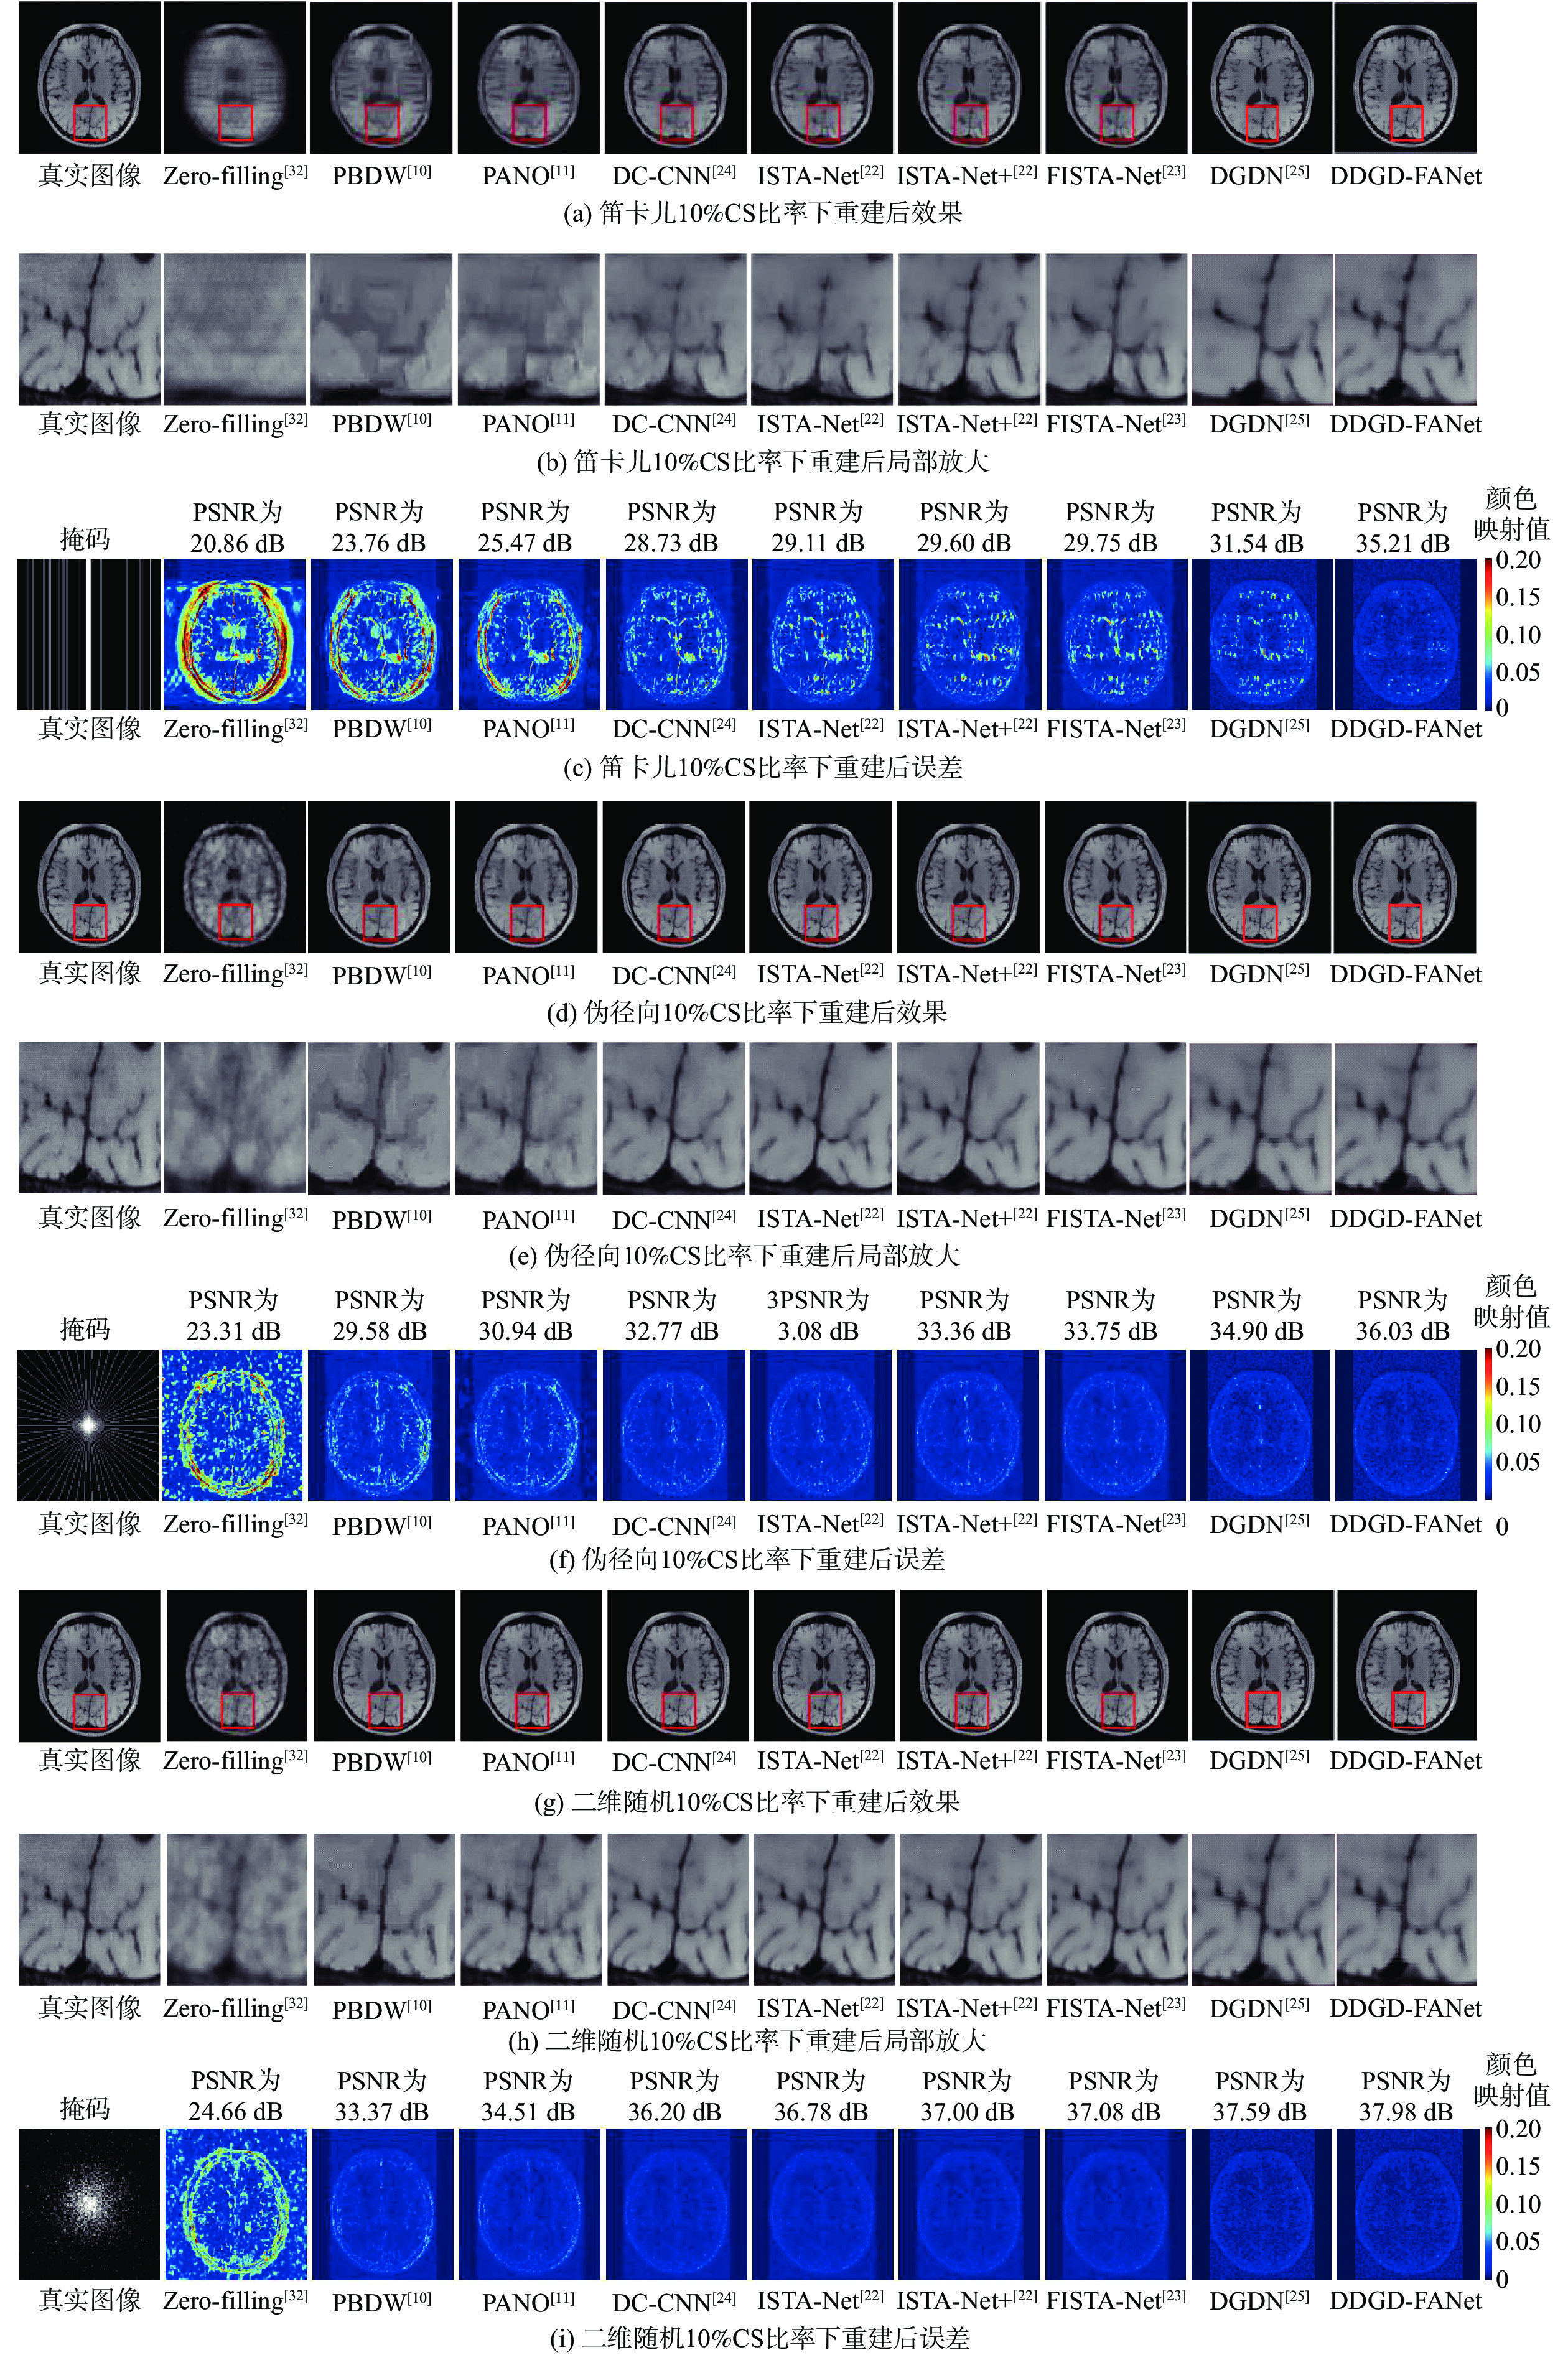

虽然现有基于深度学习的压缩感知磁共振成像(CS-MRI)方法已经取得了较好的效果,但这些方法的可解释性仍然面临挑战,并且从理论分析到网络设计的过渡并不够自然。为解决上述问题,提出深度双域几何蒸馏特征自适应网络(DDGD-FANet)。该深度展开网络将磁共振成像重建优化问题迭代展开成3个子部分:数据一致性模块、双域几何蒸馏模块和自适应网络模块,不仅可以补偿重建图像丢失的上下文信息,恢复更多的纹理细节,还可以去除全局伪影,进一步提高重建效果。在公开数据集使用3种不同的采样模式进行实验,结果表明:DDGD-FANet在3种采样模式下均取得了更高的峰值信噪比和结构相似性指数,在笛卡儿10%压缩感知(CS)比率下,峰值信噪比较迭代收缩阈值算法(ISTA-Net+)、快速ISTA(FISTA)-Net和DGDN模型分别提高了5.01 dB、4.81 dB和3.34 dB。

图 3  大脑数据集上使用不同采样模式的重建效果对比

Figure 3.  Comparison of reconstruction effects using different sampling patterns in brain dataset